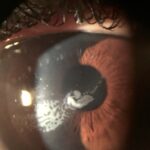

- Adelgazamiento periférico corneal circunferencial en forma de surco

- Neovacularización corneal superficial periférica

- Depósitos lipídicos.

El adelgazamiento suele comenzar en las zonas superior o supero-nasales de la córnea con la aparición de una línea blanco-amarillenta periférica, similar al arco senil. La siguiente zona que se suele afectar con mayor frecuencia es la inferior.

Posteriormente se va produciendo un adelgazamiento estromal progresivo que avanza de forma circunferencial dando lugar a un surco periférico paralelo al limbo. Conforme la enfermedad avanza aparece una fina neovascularización corneal periférica desde el limbo que cruza este surco, y que produce depósitos lipídicos en el margen anterior del surco, que suele presentar un escalón pronunciado, a diferencia del borde posterior que suele presentar un perfil más suave de transición hacia el limbo.

En el 20% de los casos puede acompañarse del llamado “pseudopterigium”, que es la presencia de una lesión conjuntival similar al pterigium, pero que aparece en meridianos diferentes al horizontal. Se piensa que es una lesión característica de la enfermedad y que puede preceder al adelgazamiento estromal.

También se han descrito la formación de quistes intracorneales en las zonas de adelgazamiento por rupturas focales de la membrana de Descemet durante el curso de la enfermedad(3).